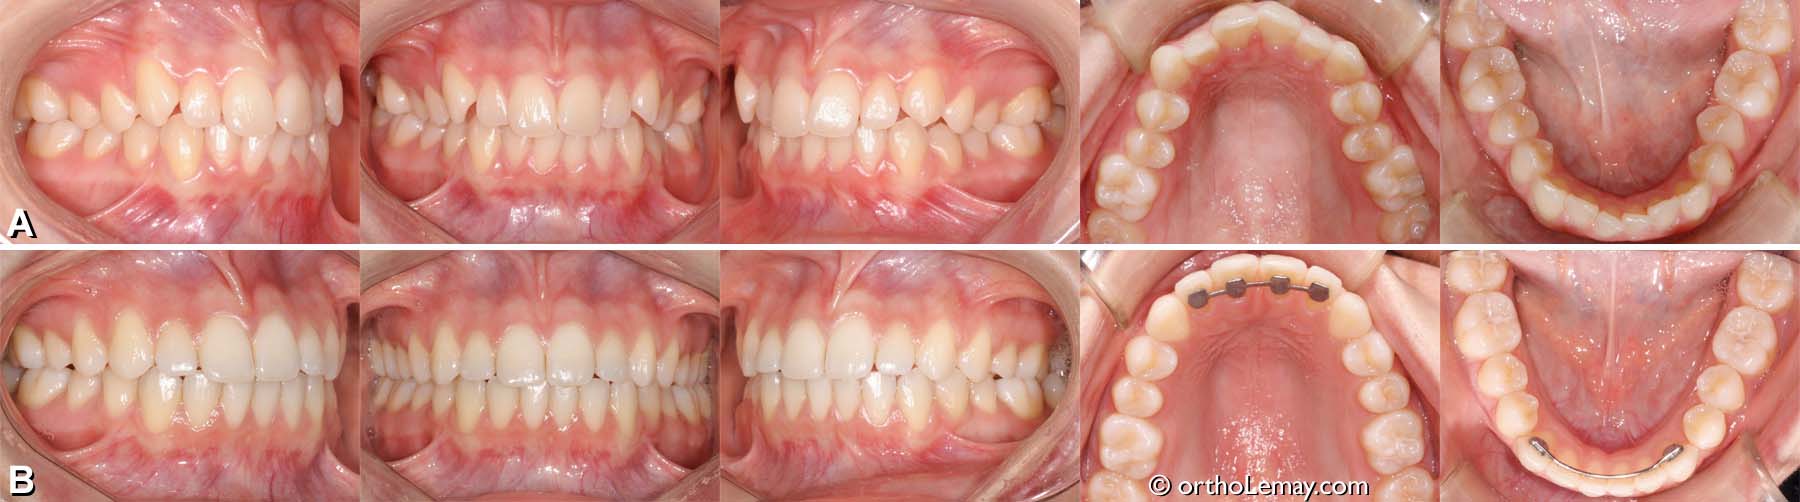

Exemple de traitement de malocclusion classe 1 (18)

(A) Malocclusion dentaire classe 1, overbite excessif, manque d’espace et déviation des lignes médianes.

(B) Après le traitement, le surplomb est corrigé, les lignes médianes alignées et les dents logées convenablement dans les arcades.